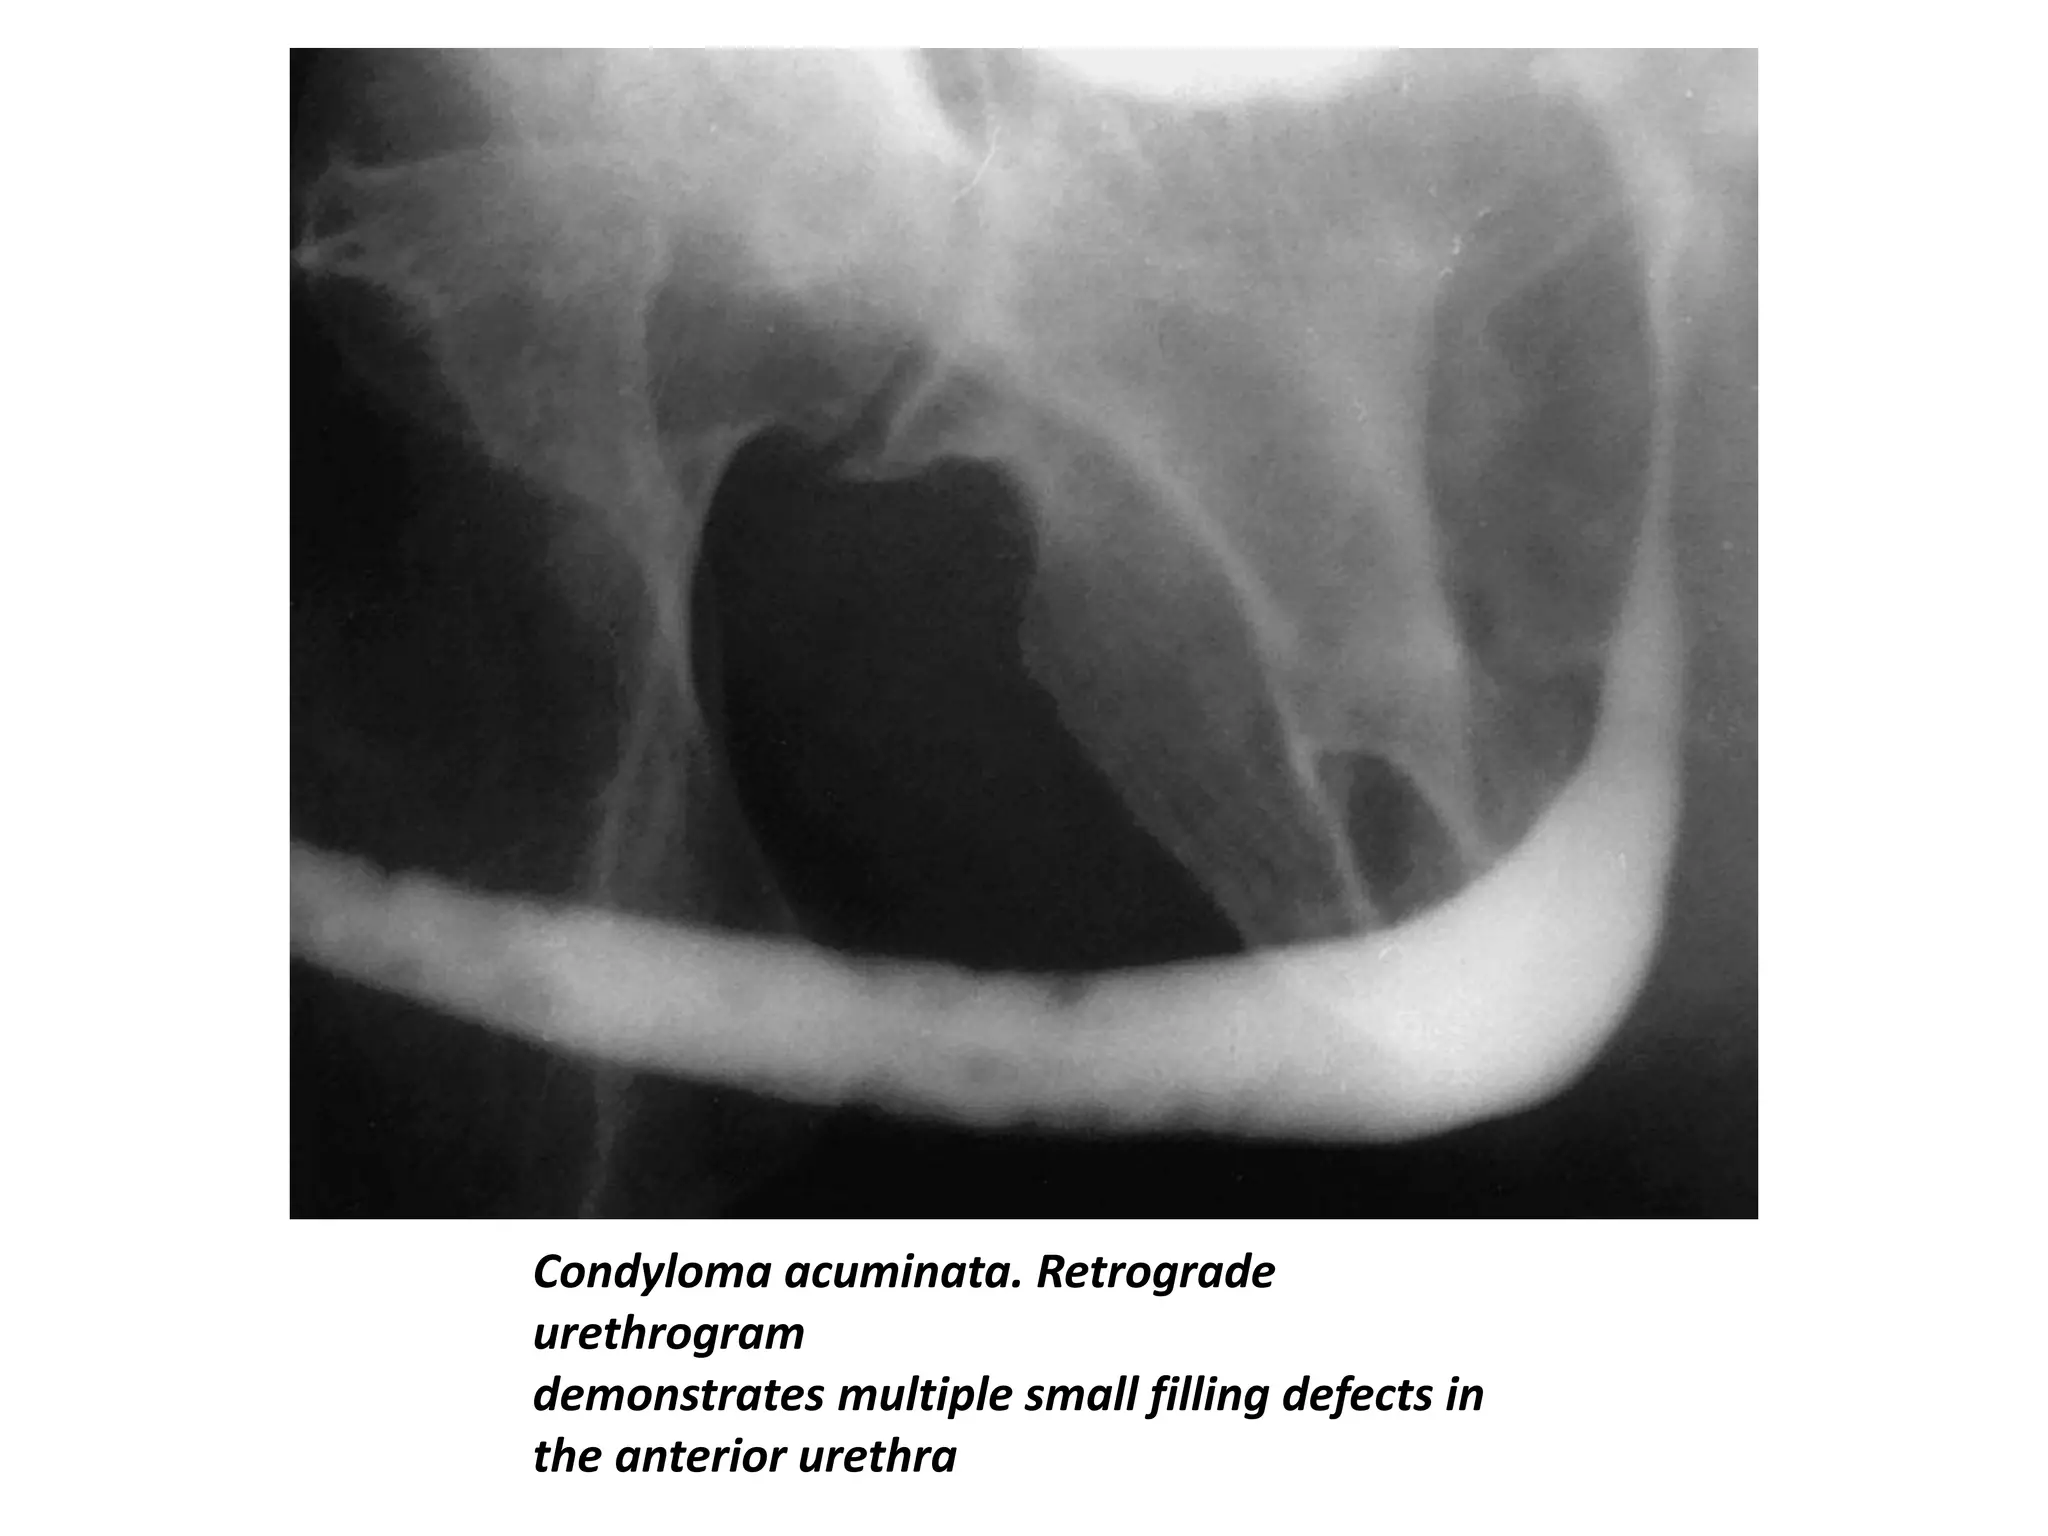

Condyloma Acuminata

• Condyloma acuminata are caused by viral infection and

produce soft, sessile, squamous papillomas on the

penile glans and shaft and the prepuce.

• Urethral involvement occurs in 0.5%–5% of male

patients.

• The use of catheterization, instrumentation, and

retrograde urethrography is not recommended

because of the possibility of retrograde seeding.

• The diagnostic procedure of choice is voiding

cystourethrography.

• The typical urethrographic findings are multiple

papillary filling defects in the anterior urethra.

Condyloma acuminata. Retrograde

urethrogram

demonstrates multiple small filling defects in

the anterior urethra